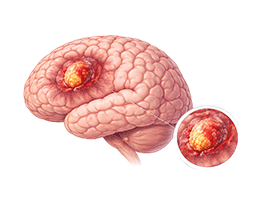

뇌종양 (Glioma)